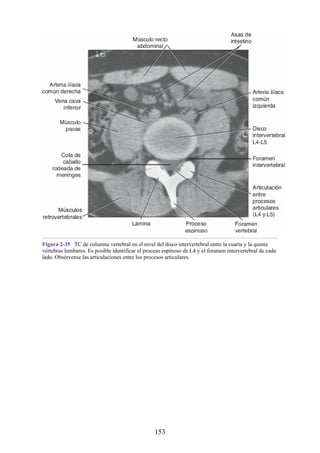

Notas clínicas

Lesiones ligamentosas